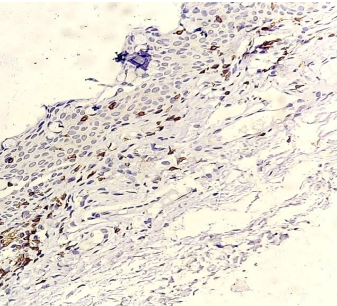

CD20+ cells stained brown (magnification 40X) on immunohistochemistry.